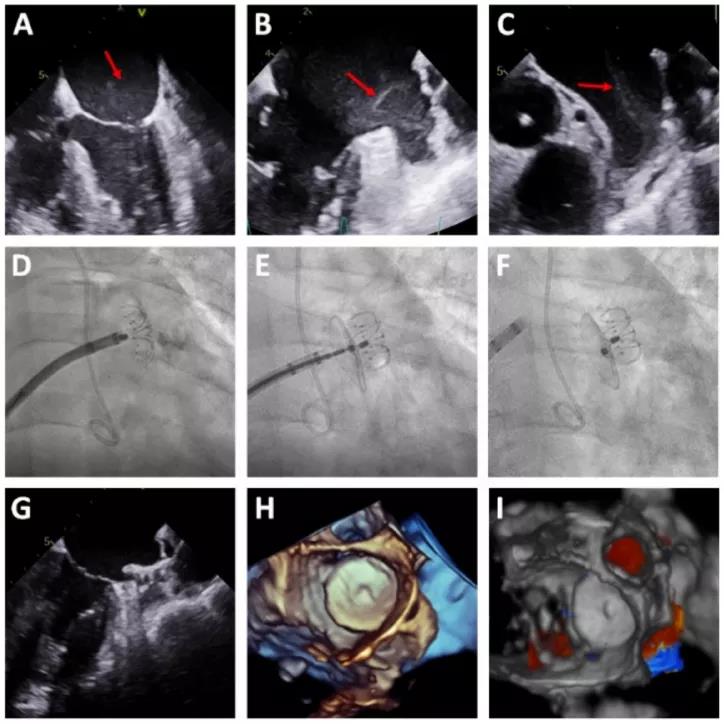

图1. (A-C)TEE下显示云雾状血栓形成;(D-F)TEE指导下进行左心耳封堵;(G)TEE造影确认封堵良好;(H-I)3D-TEE显示无残余分流